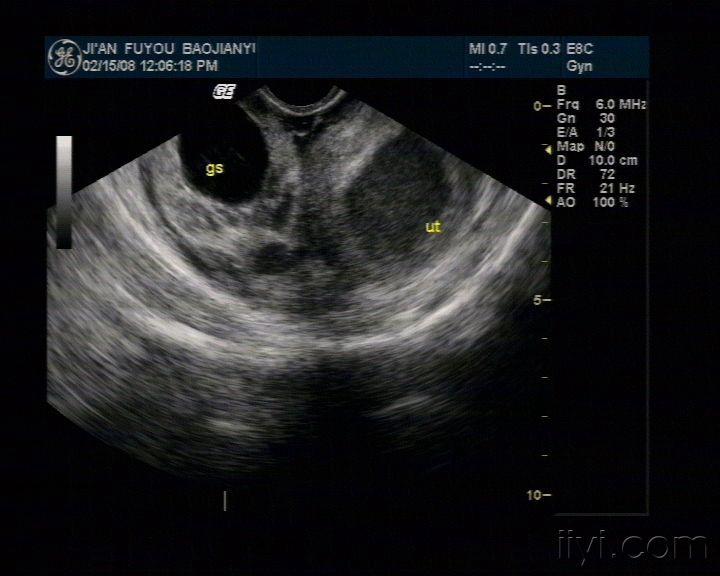

子宫位置:后位,大小约66*68*62mm,轮廓清晰,形态正常,肌层回声均匀。宫腔内见38*34mm暗区,其内见大量光点。

右侧附件区见混合回声光团,形态不规则,边界不清,内见类孕囊结构,大小47*27mm,见胎儿及原始心血管搏动,头臀长30mm。子宫直肠窝见液性暗区,最大厚径为21mm。

1. 右侧附件区混合性包块--宫外孕

2. 盆腔积液

3. 宫内无回声区,考虑宫腔积血